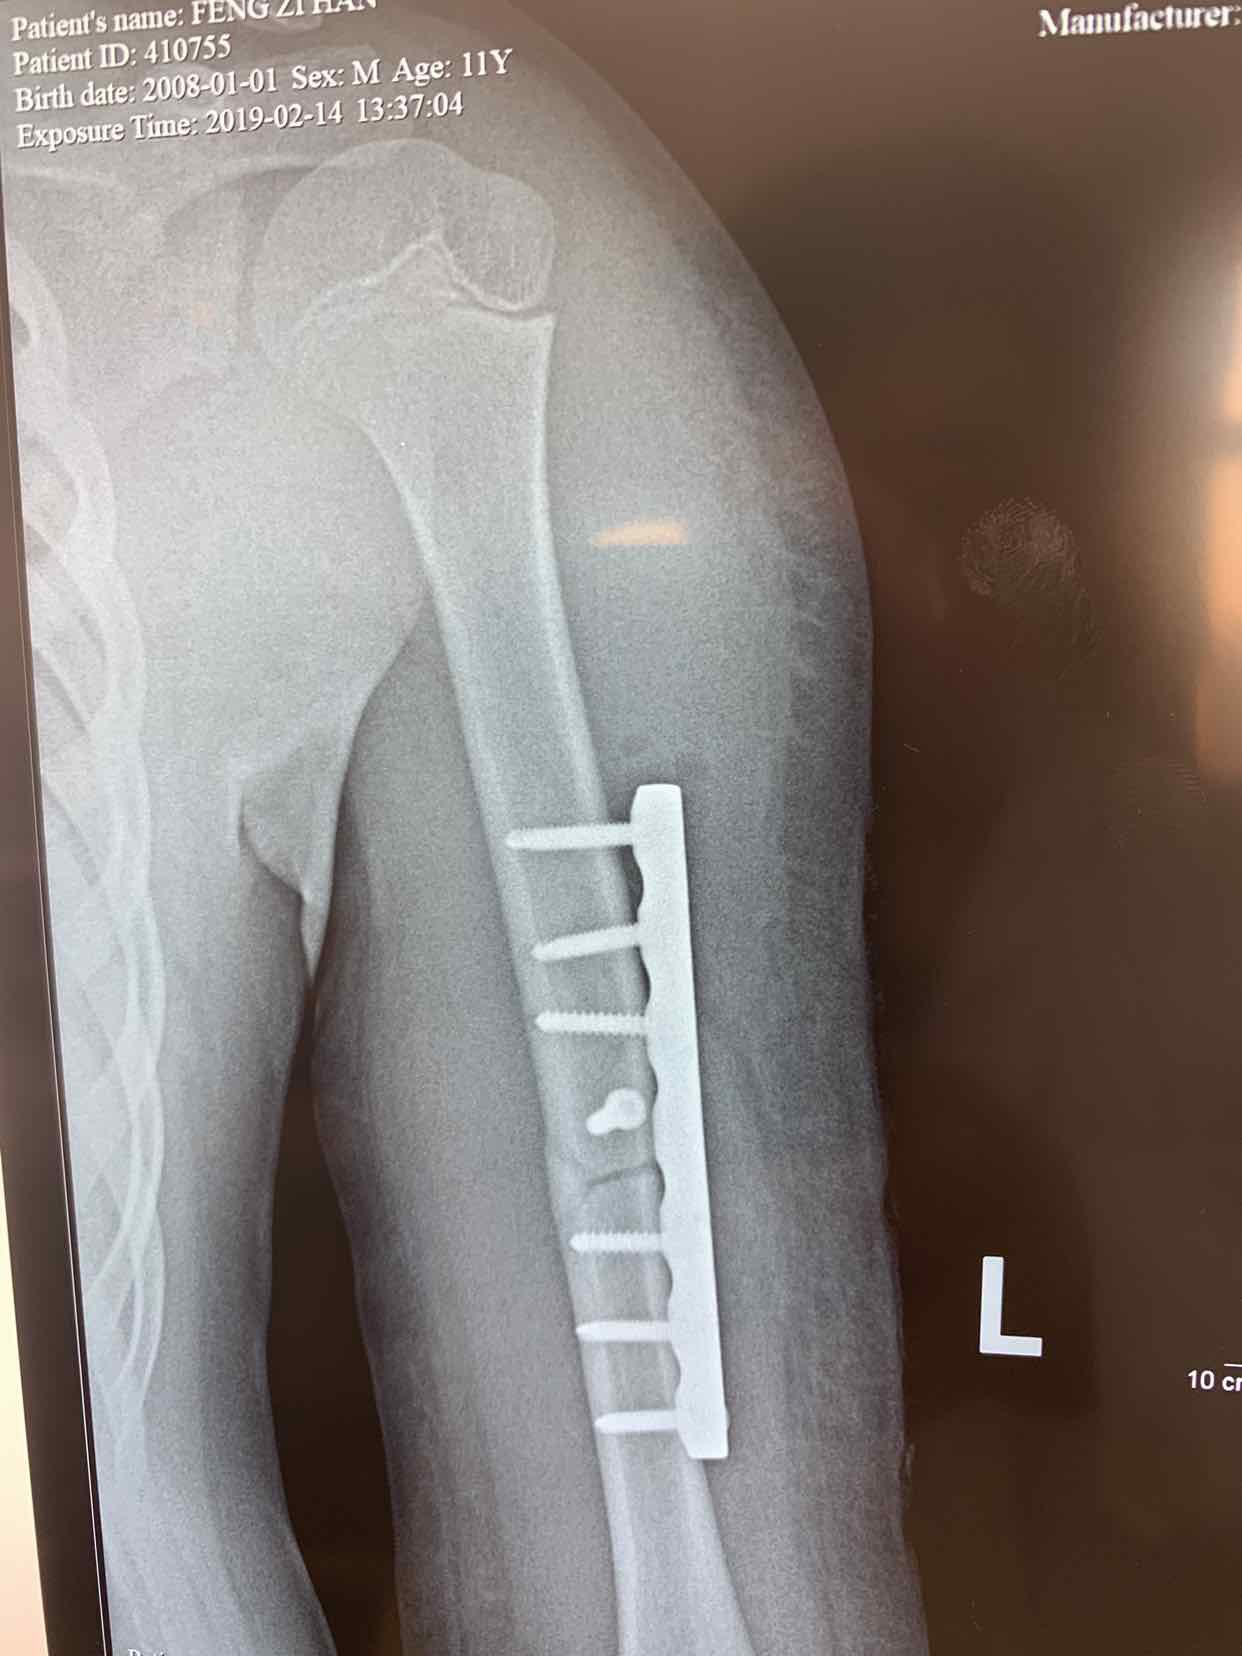

诊断为左侧肱骨中段骨折。全麻下行切开复位内固定术。术中局部应用拉力螺钉固定骨折端,安放六孔锁定钢板内固定,效果不错。术后早期就可以活动了。